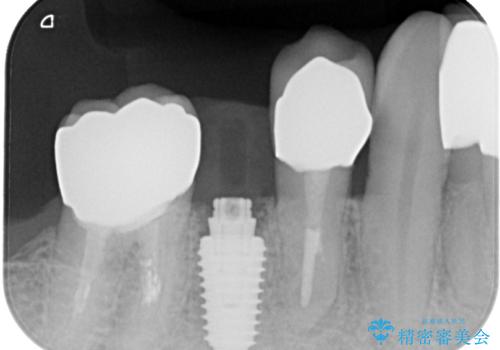

- 奥歯に装着していたクラウンが外れてしまったとのことで来院された患者様です。

診察したところ、歯根に破折線が確認され抜歯が必要な状態でした。

歯肉や歯槽骨の状態は良好であったため、抜歯即時埋入インプラントによる補綴治療を行うこととしました。

抜歯、インプラント埋入、仮歯の装着を1度に行うことができ、治療終了までわずか3か月で終えることができました。